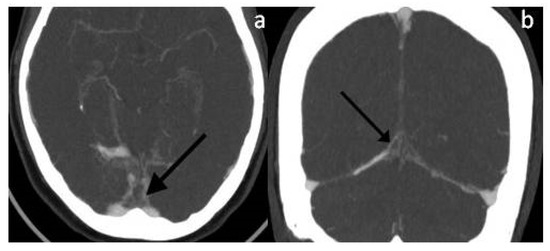

2. Case Presentation